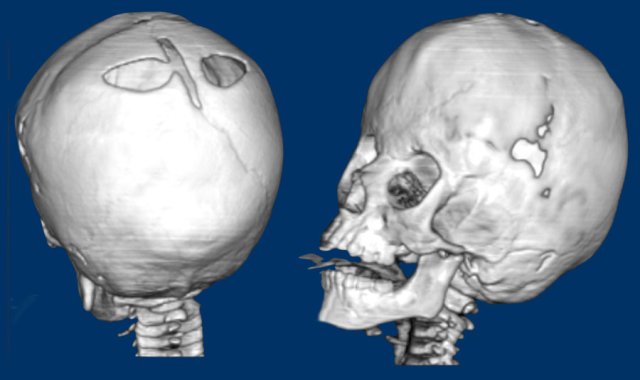

Saethre-Chotzen syndrome. At two months of age there is a bilateral coronal synostosis with a severely deformed head shape. The fontanel is grossly enlarged.

Same patient as above.

At three years old there is microcephaly from a near pan-synostosis.

Note enlarged bilateral parietal foramina.

Three-month-old with Pfeiffer syndrome.

There is a bicoronal synostosis with enlarged anterior and mastoid fontanels.

Temporal bulging give rise to a trilobate appearance, also called ‘clover leaf deformity’.

Note the ventriculomegaly with periventricular edema.